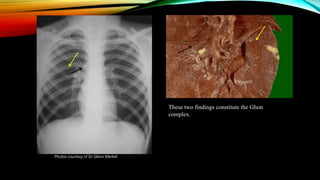

These two findings constitute the Ghon

complex.

Photos courtesy of Dr Glenn Merkel

INFECCIÓN POR M.TUBERCULOSIS. • Los macrófagos fagocitan a las micobacterias  forma granulomas que mantienen contenido al bacilo. El tejido del interior del medio muere como resultado, proceso conocido como “ necrosis caseosa” • A esta zona se le llama FOCO DE GHON (foco pulmonar inicial) • Aunque M. tuberculosis puede sobrevivir en su interior, su crecimiento es inhibido por : - Por las baja presión de oxígeno. - La presencia de un ph ácido Pueden permanecer en estado latente durante meses años o en más del 90% todas las vida.

These two findingsconstitute the Ghon complex. Photos courtesy of Dr Glenn Merkel